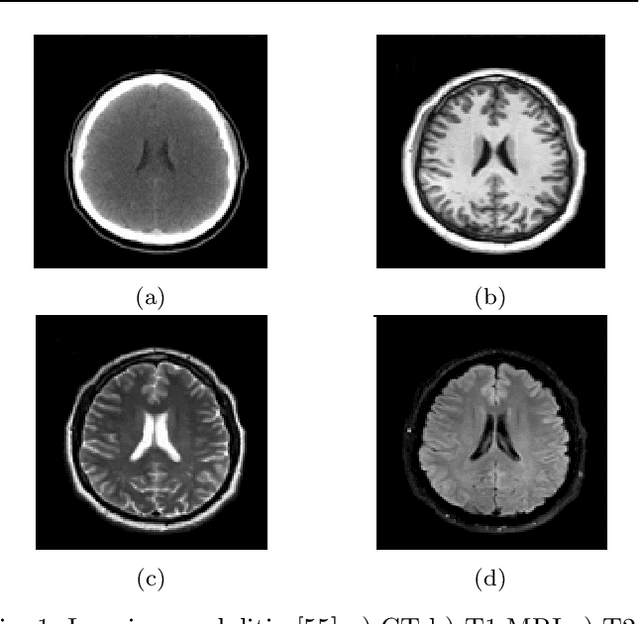

Glioma is the most deadly brain tumor with high mortality. Treatment planning by human experts depends on the proper diagnosis of physical symptoms along with Magnetic Resonance(MR) image analysis. Highly variability of a brain tumor in terms of size, shape, location, and a high volume of MR images makes the analysis time-consuming. Automatic segmentation methods achieve a reduction in time with excellent reproducible results. The article aims to survey the advancement of automated methods for Glioma brain tumor segmentation. It is also essential to make an objective evaluation of various models based on the benchmark. Therefore, the 2012 - 2019 BraTS challenges database evaluates state-of-the-art methods. The complexity of tasks under the challenge has grown from segmentation (Task1) to overall survival prediction (Task 2) to uncertainty prediction for classification (Task 3). The paper covers the complete gamut of brain tumor segmentation using handcrafted features to deep neural network models for Task 1. The aim is to showcase a complete change of trends in automated brain tumor models. The paper also covers end to end joint models involving brain tumor segmentation and overall survival prediction. All the methods are probed, and parameters that affect performance are tabulated and analyzed.